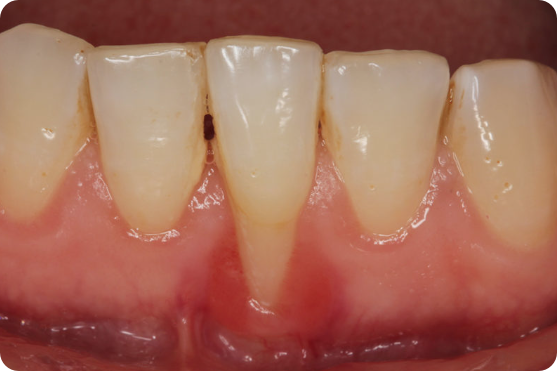

Diş eti çekilmesi bir durumdur, hastalık değildir. Diş eti çekilmesi, diş etlerinin geriye doğru çekilerek dişin kök kısmının açığa çıkması durumudur. Genellikle diş eti çekilmesi dişlerin dudaklara bakan yüzeyinde diğer yüzeylerine oranla çok daha fazla görülmektedir.

Bu durum, diş hassasiyetine, çürük oluşumuna ve ilerleyen zamanlarda ise diş kaybına yol açabilir.  Diş eti çekilmesinin birçok sebebi vardır bu sebeplerden biri de diş eti hastalığıdır. Dolayısı ile de bir ilaç tedavisi yoktur. Genel olarak diş hekimliğinde ilaç sadece takviye amaçlı reçete edilmektedir. Çoğu durumda sadece hap veya ilaç alarak bir sorunu çözemezsiniz. Bu durum agresif diş fırçalama, diş eti hastalığı, ve hatta genetik nedenlerden kaynaklanabilir. Tedavi seçeneği olarak cerrahi ve cerrahi olmayan yöntemler mevcuttur. Bazı diş eti çekilmesi durumlarında hiç çekilme olmamış gibi sonuç elde edile bilinirken çoğu vakada %100 geri kazanma sağlanamıyor. Eğer bu makaleyi sonuna kadar okursanız diş eti çekilmesi ile bağlı aklınızdaki tüm sorulara cevap bulmuş olursunuz.

Diş eti çekilmesi genellikle akut gelişen bir durum değildir, diş eti çekilmesi sebebe bağlı olarak aylar ve ya yıllar içerisinde oluşmaktadır. Diş eti çekilmesi ya hastanın kendisi tarafından ya da muayene sırasında diş hekimi tarafından teşhis edilmektedir. Ön bölge dişlerde olan diş eti çekilmesi arka bölge dişlere göre hastalar tarafından daha çabuk fark edilebilmektedir. Diş eti çekilmesini fark edilebilmesi kişinin farkındalık düzeyi ile de alakalıdır.